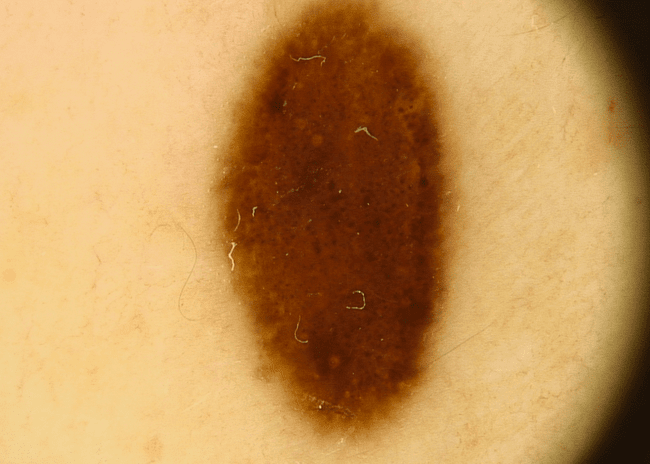

Znane wszystkim zwykłe pieprzyki to inaczej znamiona barwnikowe powstałe w wyniku namnażania się komórek pigmentowych – głównie pod wpływem promieniowania UV. Większość z nich jest neutralna dla zdrowia i co najwyżej tworzy problem jako defekt kosmetyczny.

Zwykłe znamię barwnikowe - łagodny pieprzyk zdjęcie dermatologiczneZwykłe znamię barwnikowe - łagodny pieprzyk zdjęcie dermatologiczne

Zwykłe znamię barwnikowe - typowy pieprzyk zdjęcie medyczneZwykłe znamię barwnikowe - typowy pieprzyk zdjęcie medyczne

Zwykłe znamię barwnikowe - pieprzyk łagodny zdjęcie kliniczneZwykłe znamię barwnikowe - pieprzyk łagodny zdjęcie kliniczne

Zwykłe znamię barwnikowe - typowy pieprzyk zdjęcie dermatologiczneZwykłe znamię barwnikowe - typowy pieprzyk zdjęcie dermatologiczne

Zwykłe znamię barwnikowe - łagodny pieprzyk zdjęcie medyczneZwykłe znamię barwnikowe - łagodny pieprzyk zdjęcie medyczne

Zwykłe znamię barwnikowe - pieprzyk łagodny zdjęcie dermatologiczneZwykłe znamię barwnikowe - pieprzyk łagodny zdjęcie dermatologiczne